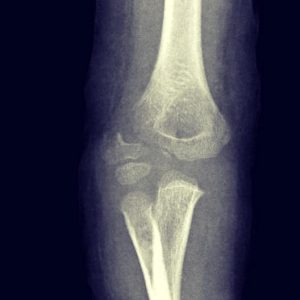

- Fracturas de codo

- Fractura supracondílea

- Fractura de cóndilo humeral

fractura de condilo humeral

Fractura supracondílea de humero